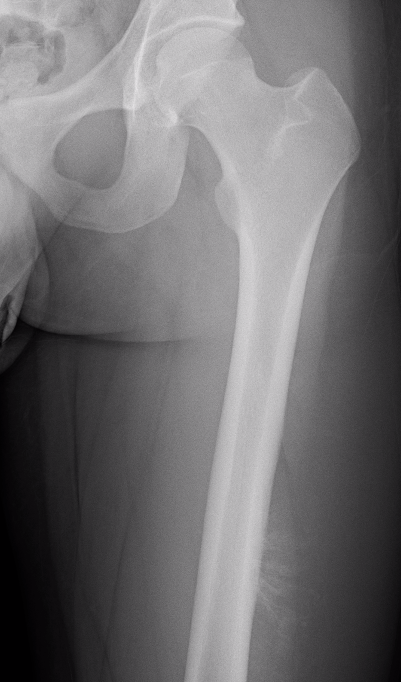

Xray

Often diaphyseal

- diffuse permeative destruction

- can be subtle

Periosteal reaction

- Codman's triangle / onion skinning / sunburst appearance

Ewing's acomion Ewings lesser trochanter

Ewing proximal femur

Ewing's femoral diaphysis, subtle on xray with large soft tissue component